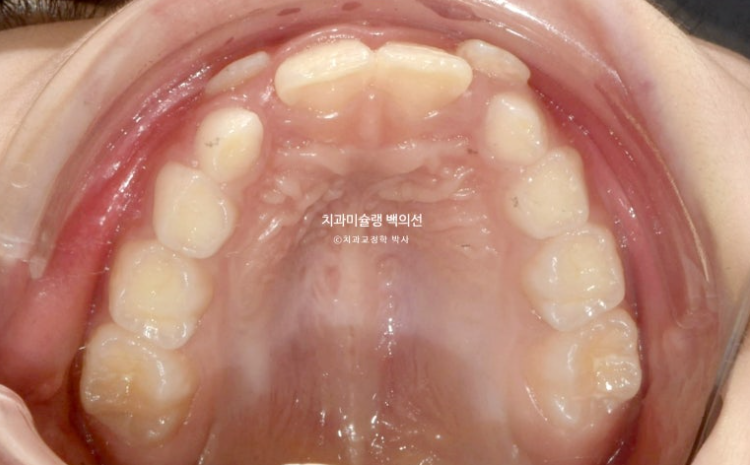

악궁확장을 통해 넓어진 악궁

23.11

아래 앞니도 배열이 되었고 아래는 벌써 송곳니가 제자리로 잘 올라오고 있습니다.

이제 본격적으로 아래턱 성장을 시작하는 MA단계에 접어듭니다.